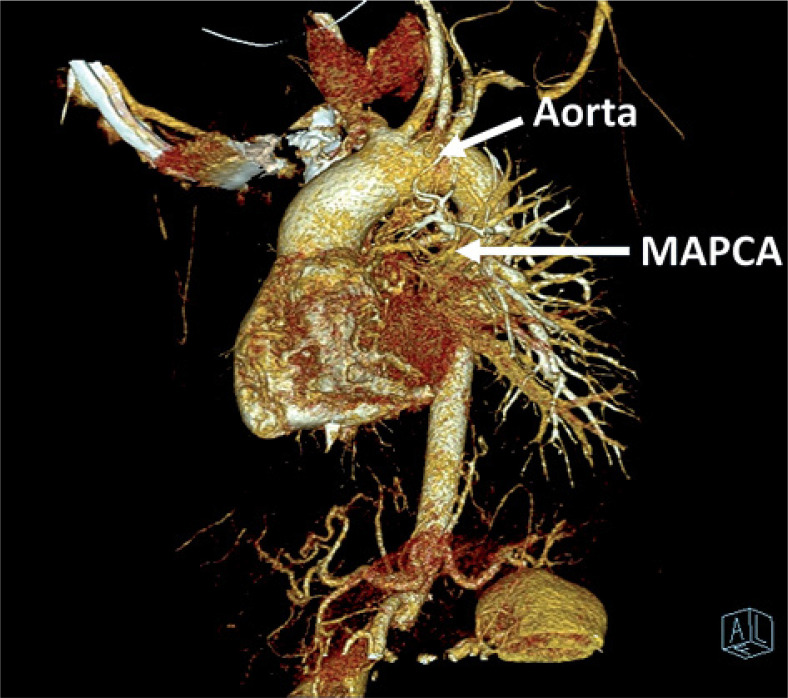

Purpose: Major aortopulmonary collateral arteries (MAPCAs) are rare congenital anomalies with significant clinical implications, often associated with congenital heart diseases like tetralogy of Fallot (TOF) and pulmonary atresia (PA). This study aimed to investigate the clinical, echocardiographic, and radiologic characteristics of MAPCAs in patients with congenital heart diseases admitted to our clinic between 2016 and 2023.

Material and methods: A retrospective analysis of 46 cases was conducted using chest computed tomography exams performed on a dual-source 128-slice CT scanner. Clinical data and radiologic characteristics were collected and analysed.

Results: The study revealed a strong correlation between congenital heart diseases and the presence of MAPCAs, with TOF, PA, and ventricular septal defect (VSD) being the most common, and it indicated that these collaterals may exist with non-diagnosed congenital heart disease. Tricuspid regurgitation and aortic insufficiency were the predominant echocardiographic findings. Radiologically, MAPCAs primarily originated from the descending aorta (type II) in 85% of cases, and their sizes ranged from ≤ 3 mm to > 10 mm, with an average of 5 mm.